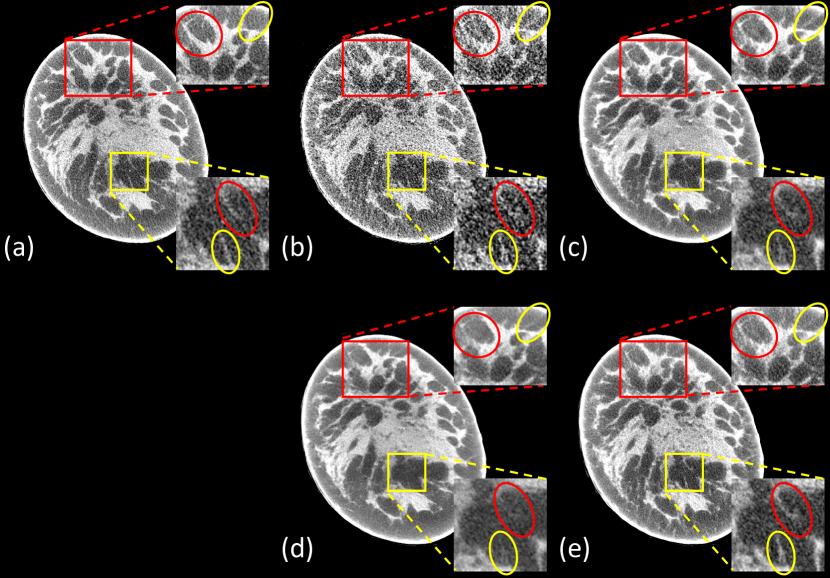

To visualize the performance of different methods, a few representative slices were selected from the testing dataset. Figs. 2 and 3 show results reconstructed using different methods from 75-view cone-beam projections. For better evaluation of the image quality, the regions of interest (ROIs) marked in the red/yellow boxes in both figures are magnified. Three metrics, including Peak Signal to Noise Ratio (PSNR) [46], SSIM [42], and MAE [41], were computed for quantitative assessment. The quantitative results are shown in Table I.

Our proposed DEER network produced few-view denoising results comparable or superior to that from both image-domain methods. All of the deep-learning methods could effectively remove streak artifacts introduced by the few-view constraint. Particularly, the DEER network produces better reconstructions in the selected ROIs. Both image-domain methods tend to smooth out some subtle details embedded in the noisy background due to insufficient data. For example, in Fig. 2, the breast feature inside the yellow circle is hardly distinguishable in Fig. 2 (c) and (d). Also, in Fig. 3, the feature in the red circle of red ROI and the features in the yellow ROI are hardly visible in the image reconstructed by FBPConvNet.

For the Residual-CNN method, the intensity of certain features is dimmer than expected in the reconstructed breast slices (feature in the yellow circle of Fig. 2, and features in the yellow ROI of Fig. 3). Moreover, the FBP method is associated with artifacts that do not exist in the ground-truth images, and in some cases, the image-domain methods cannot remove these artifacts through convolutional operations. For example, the artifact in the yellow circle of red ROI in Fig. 3 is clearly visible in the image produced by Residual-CNN, but this artifact is mostly removed by DEER through a learnable network-based reconstruction algorithm.

For the quantitative assessments, DEER had better SSIM and MAE values and a slightly lower PSNR value than FBPConvNet. FBPConvNet achieved the best PSNR value due to the implementation of the Mean Squared Error (MSE) based objective function. However, the literature has discussed that higher PSNR values do not guarantee the denoising performance, especially the textural/visual similarities relative to the ground-truth images [47, 5]. Also, it should be noted that since both FBPConvNet and residual-CNN only use a single loss function for optimization, these two methods may be subject to potential losses in visual performance. Both loss functions have their own limitations, and one should not solely rely on them for estimating image quality [48, 49]. Even though DEER does not achieve significant improvements quantitatively, images reconstructed by DEER present promising visual comparisons. Moreover, as presented in Figs. 2 and 3, the images reconstructed by FBPConvNet appear over-smoothed with less visual image texture, which is not desirable in clinical diagnosis. Lastly, the implementation of WGAN framework may negatively affect the quantitative measurements but it provides better recovery of subtle details and structural features [5, 50]. Compared with the other deep learning methods, DEER demonstrates a competitive performance in removing artifacts and reserving subtle but vital details compared with the other methods. In terms of reconstruction time, DEER takes about 0.1422 seconds to reconstruct a single 2D slice () on an NVIDIA Titan RTX GPU.